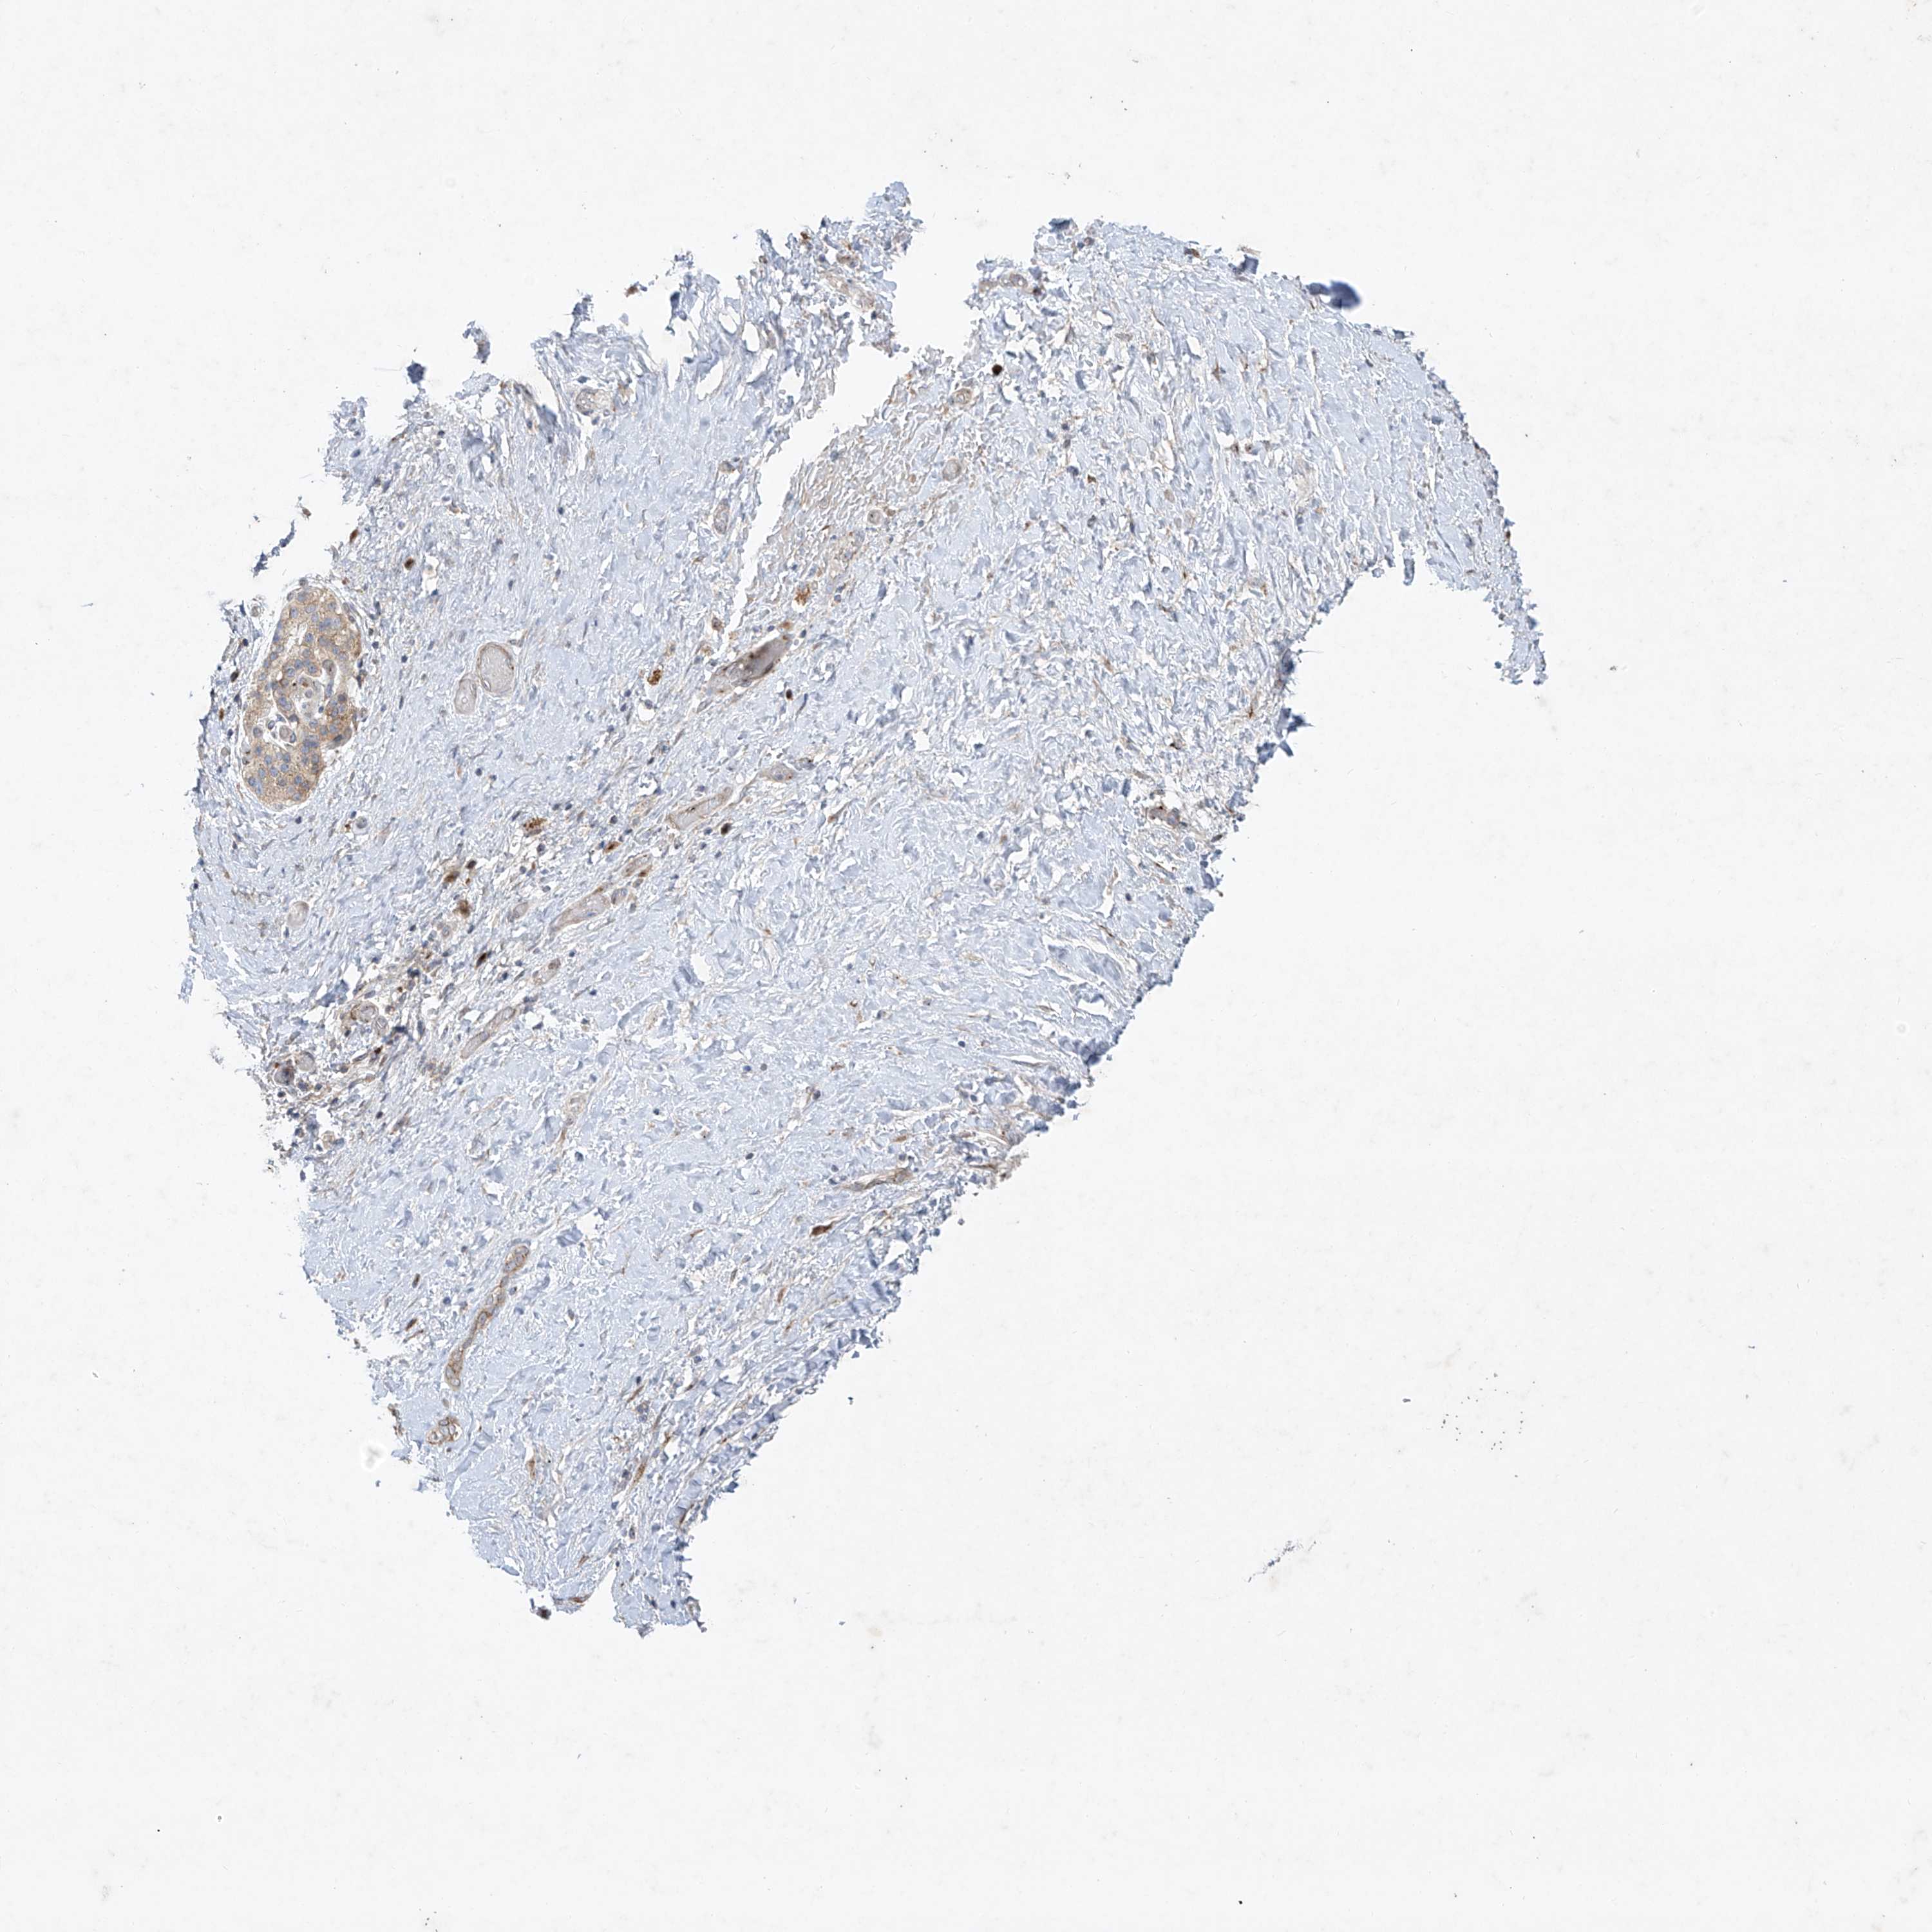

PANCREATIC CANCER - Protein expressioni

A mouse-over function shows sample information and annotation data. Click on an image to view it in a full screen mode. Samples can be filtered based on level of antibody staining by selecting one or several of the following categories: high, medium, low and not detected. The assay and annotation is described here.

Note that samples used for immunohistochemistry by the Human Protein Atlas do not correspond to samples in the TCGA dataset.

Antibody stainingi

Antibody staining in the annotated cell types in the current human tissue is reported as not detected, low, medium, or high, based on conventional immunohistochemistry profiling in selected tissues. This score is based on the combination of the staining intensity and fraction of stained cells.

Each image is clickable and will lead to virtual microscopy that enables deeper exploration of all samples and also displays staining intensity scores, fraction scores and subcellular localization as well as patient and tissue information for each sample.

Antibody HPA030164

Antibody HPA030165

Antibody HPA030166

Adenocarcinoma, NOS